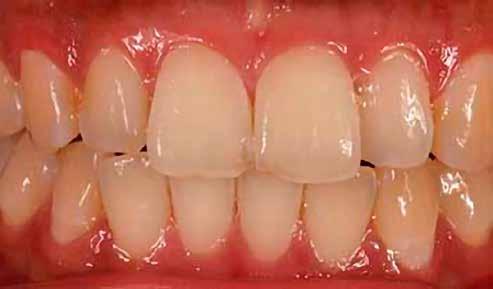

A 19 éves hölgypáciens azzal a kéréssel jelentkezett a rendelőnkbe, hogy szebb fogakat szeretne. Az első konzultáció alkalmával megkérdeztük, hogy mi zavarja leginkább a fogazatának jelenlegi megjelenésében, valamint azt is megbeszéltük vele, hogy milyen végeredmény elérése esetén lenne maradéktalanul elégedett. Ebben az esetben a kezelési célokat az alábbiakban határoztuk meg:

A páciens fogazata esztétikai megjelenésének és funkcionális működésének a lehető legtöbb, saját foganyag megtartása mellett történő helyreállítása (1. és 3. ábra). A lehető legideálisabb esztétikai végeredmény elérése érdekében néhány esetben a fogak alakjának módosítá -

sára is szükség van (2. és 4. ábra).

A kezelés megtervezése során kifejezett jelentősége van annak, hogy jó kommunikáció legyen a páciens, a fogorvos és a fogtechnikus között. A páciens leendő fogazatának természetes megjelenését a kezelésben részt vevő team szakmai felkészültsége, gyakorlati tapasztalata és a kezelés sikerességének irányába történő elkötelezettsége biztosítja. A beavatkozások megkezdése előtt megtörtént a páciens anamnézisének a felvétele, valamint a klinikai kivizsgálását is elvégeztük. Ezt követően lenyomatokat készítettünk a kiindulási állapotról, majd a kiindulási helyzetet extra- és intraorális fotók segítségével is rögzítettük (13. a-c. ábra).